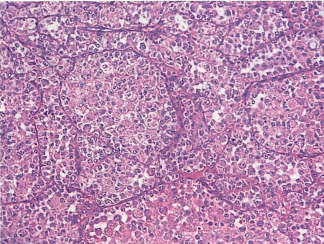

光镜下观察组织形态如图所示,考虑诊断为

-